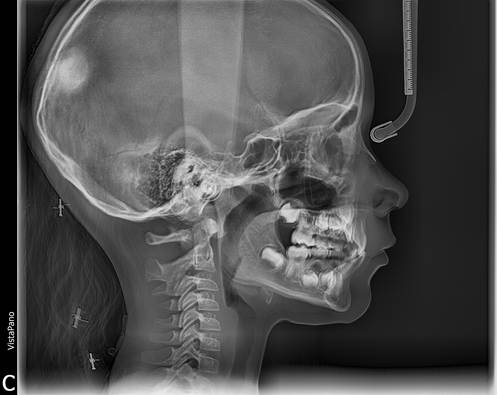

Figura 10. Telerradiografía lateral

La telerradiografía lateral de cráneo muestra una relación esqueletal de Clase I. Los incisivos superiores permanentes ocluyen por lingual de los incisivos inferiores permanentes.